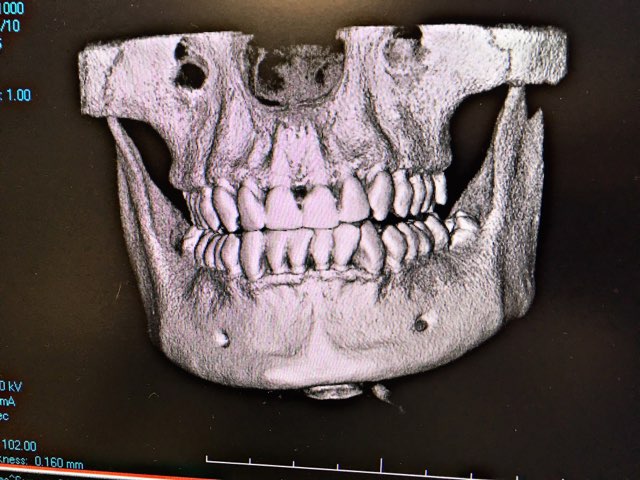

CBCT 3D Scanner

CBCT

Fenwick Dental has Latest CBCT scanner called Prexion Excelsior. With traditional dental x rays, one can only view images 2 dimensionally. With our CT scan our clinician can view images 3 dimensionally, so that we can diagnose pathology better. With increased visibility and quality of images we are able to serve you better.

Indications of a CT scan

• For implant placement

• To diagnose TMJ issues

• To diagnose Airway issues.

• To diagnose infection at root part of the tooth

• To diagnose bone pathology

• To diagnose sinus pathology